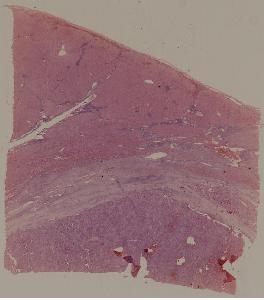

69. Hepatocellular carcinoma